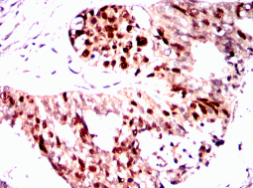

PGR Mouse Monoclonal antibody[2C11F]

PGR: progesterone receptor. This gene encodes a member of the steroid receptor superfamily. The encoded protein mediates the physiological effects of progesterone, which plays a central role in reproductive events associated with the establishment and maintenance of pregnancy. This gene uses two distinct promotors and translation start sites in the first exon to produce two isoforms, A and B. The two isoforms are identical except for the additional 165 amino acids found in the N-terminus of isoform A only, and mediate their own response genes and physiologic effects with little overlap. The location of transcription initiation for isoform B has not been clearly determined.

Immunogen:    Purified recombinant fragment of PGR (aa731-909) expressed in E. Coli.

IHC    1/200 - 1/1000